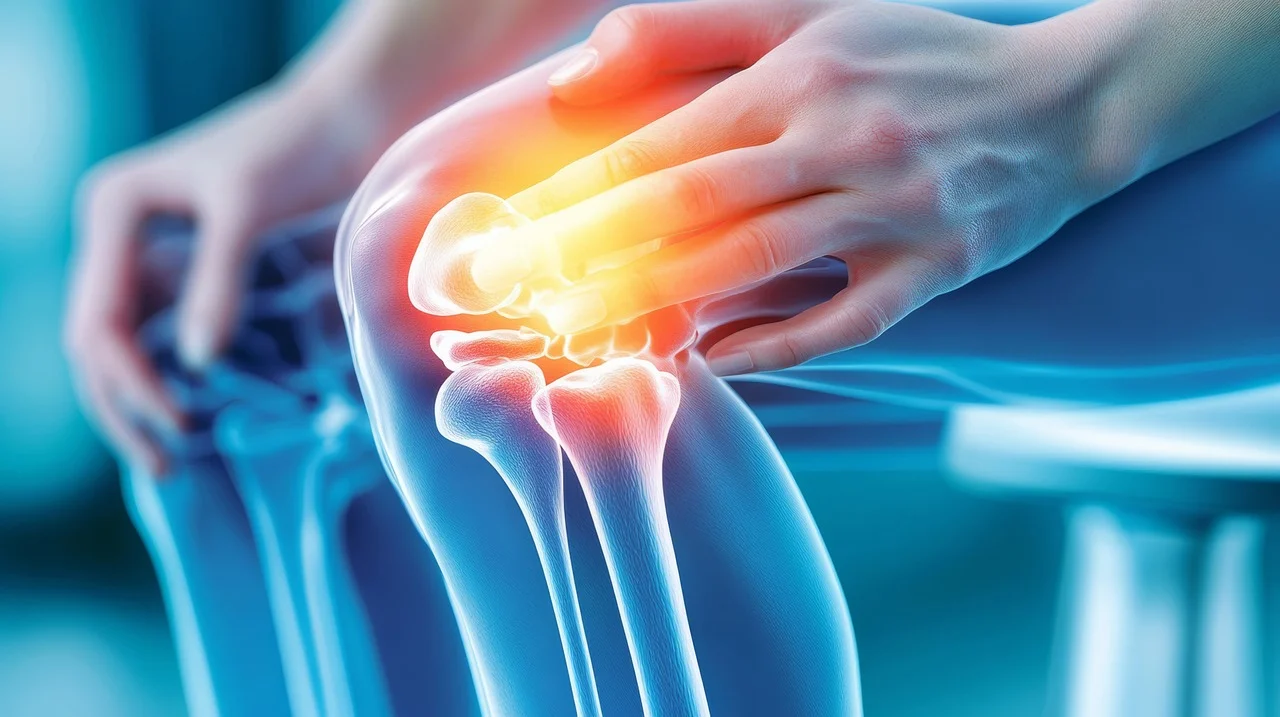

무릎 연골 손상의 원인은 다양합니다. 가장 흔한 원인 중 하나는 퇴행성 변화로 인한 관절염이에요. 나이가 들면서 연골이 점차 닳아 없어지기 때문이죠. 과도한 운동이나 무리한 활동 또한 연골 손상의 주요 원인이 될 수 있습니다. 특히 반복적인 충격이 가해지는 운동이나 갑작스러운 방향 전환은 연골에 부담을 줄 수 있습니다.

스포츠 외상으로 인한 직접적인 충격도 연골 손상을 유발할 수 있습니다. 축구, 농구 등 격렬한 운동 중 무릎 부위에 가해지는 강한 충격은 연골 파열로 이어질 수 있습니다. 이 외에도 비만으로 인한 무릎의 과부하, 잘못된 자세, 유전적인 요인 등이 복합적으로 작용하여 연골 손상을 일으킬 수 있습니다. 드물게는 감염이나 자가면역 질환이 연골 손상의 원인이 되기도 합니다. 따라서 정확한 원인을 파악하는 것이 중요하며, 이를 통해 적절한 치료 및 관리 방법을 찾을 수 있습니다.